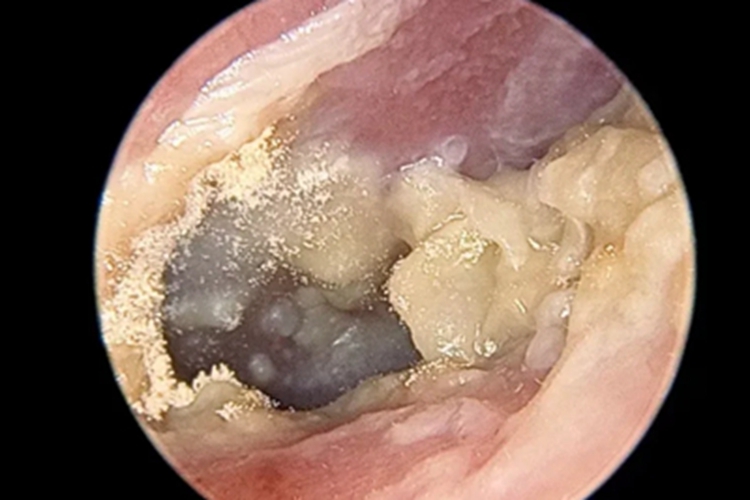

霉菌性外耳道炎的损害可发生在外耳道,其临床可表现为患者的外耳道处有大量黄白色脓液性分泌物,团块状附着于外耳道壁上,边缘有碎纸样白色鳞屑,耳朵内部黏液呈灰黑色,伴瘙痒感,以夜间为甚。